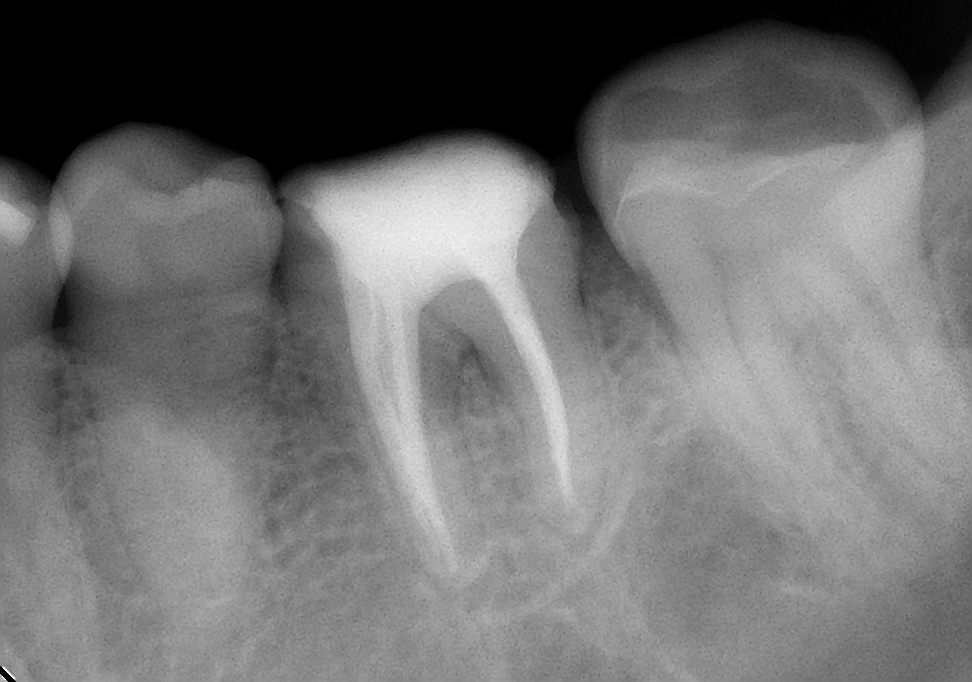

↑before ↑after

では、感染根管処置はどうかというと通常の根管治療だけで経過良好な現在生存している歯は、90%。